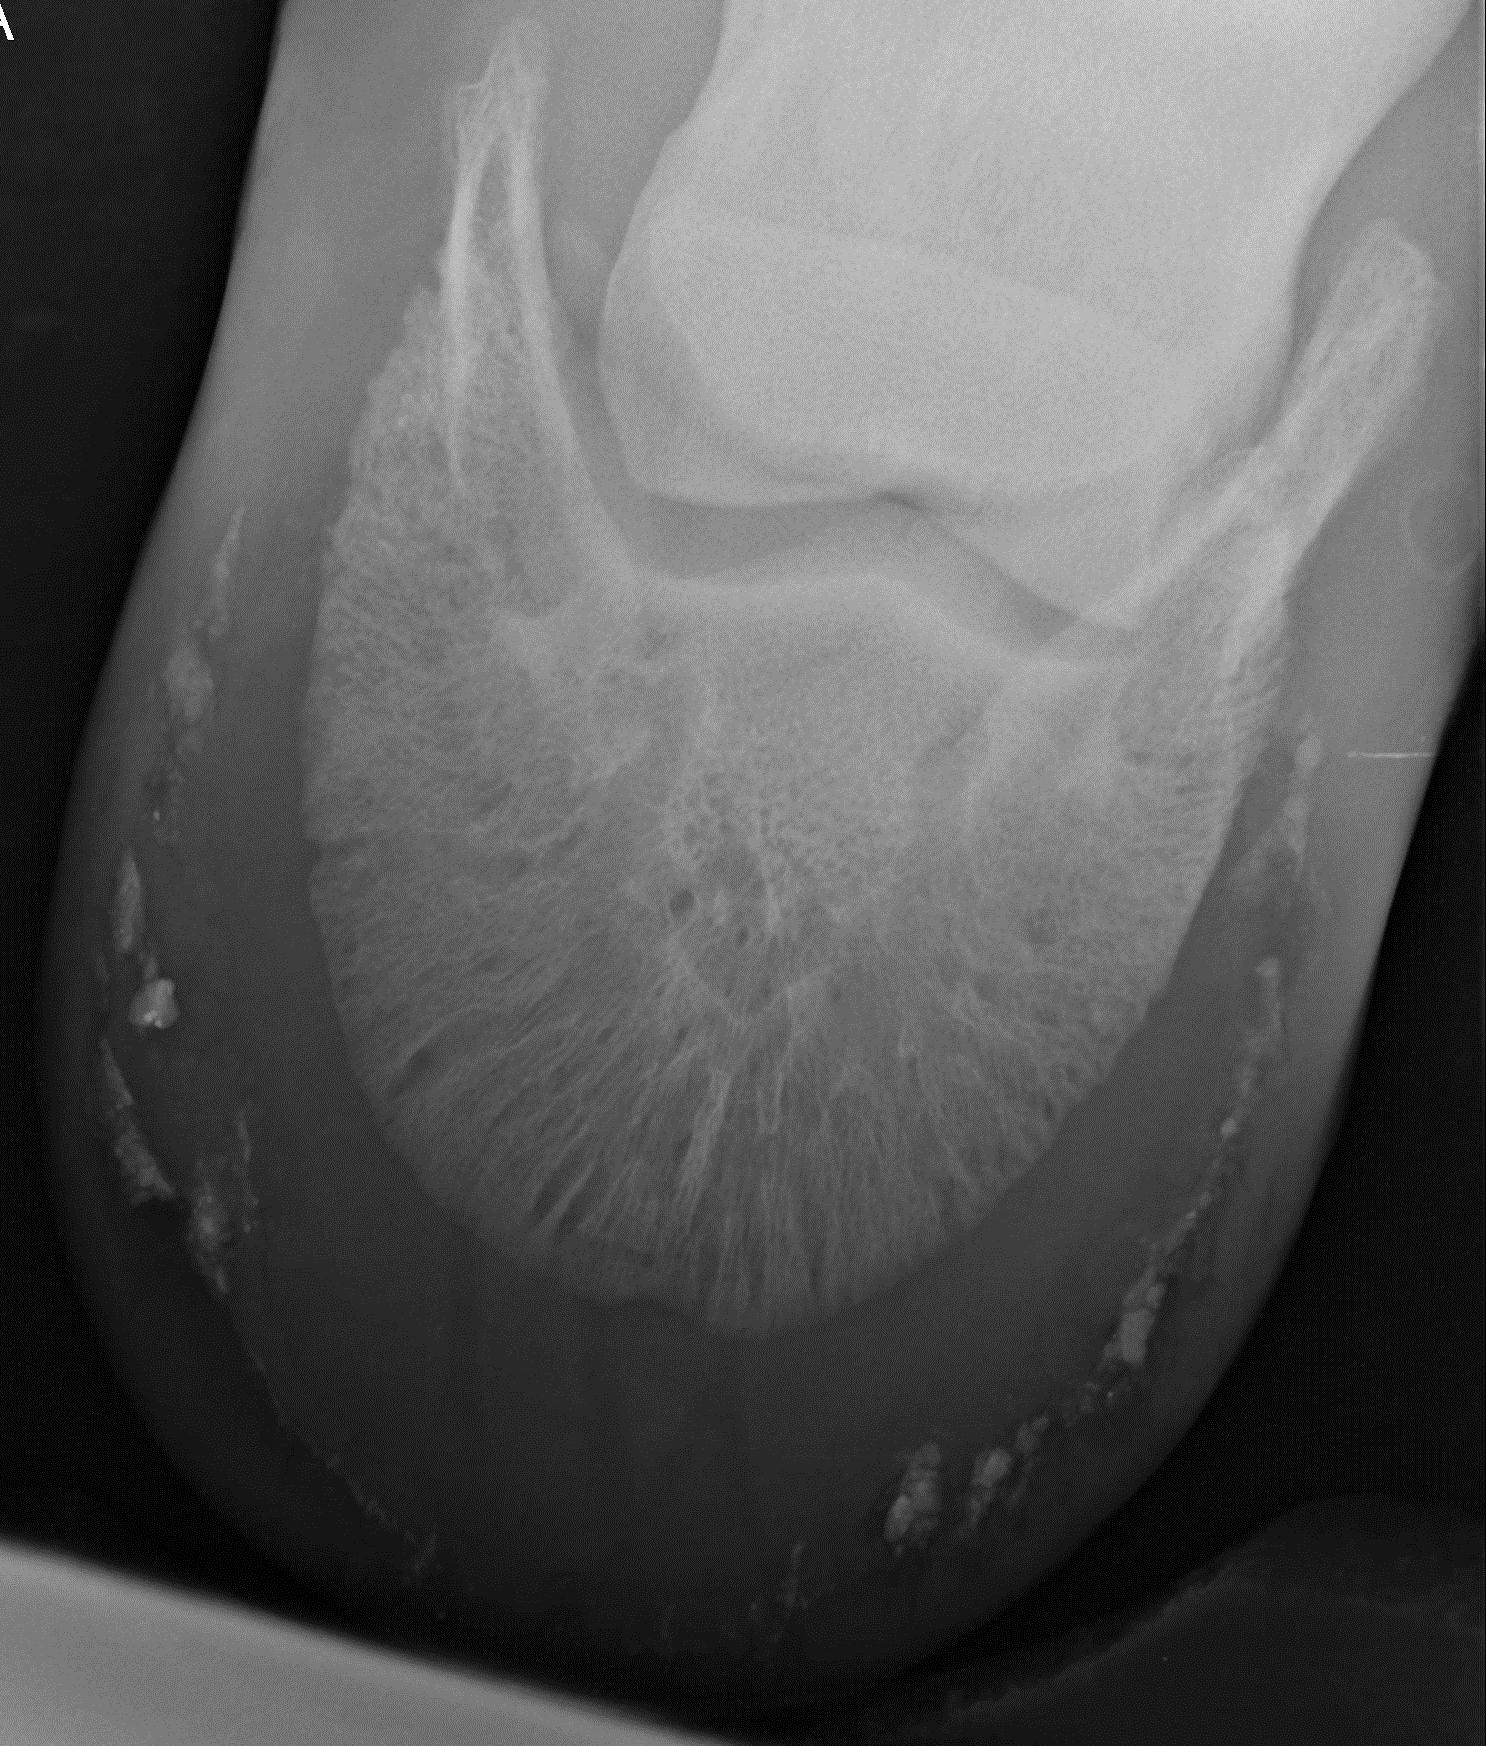

Not only can this disease destroy healthy wall, it also can lead to abscessing. X-rays are a helpful tool to expose the extent of present hoof wall disease. The radiograph in Fig. 14 is from a horse with a history of unexplained periodic abscessing. I guess this picture explains a lot. I never saw the foot in person, so I can’t say if those insults would have been visible from the outside. I would very much assume so.

Fig. 14